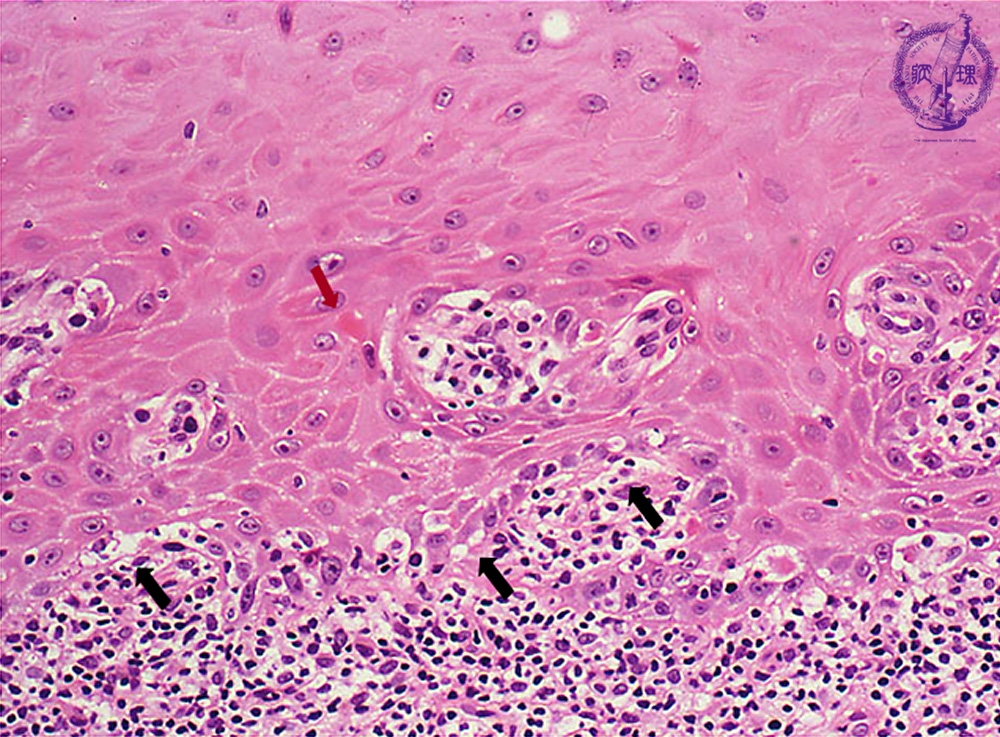

Microscopic finding (HE stain, high-power view):The basal cells show vacuolar change, or hydropic (liquefaction) degeneration (black arrows) and there is cleft formation between the epidermis and papillary dermis. Colloid bodies (degenerating keratinocytes) (red arrow) are seen in the epithelium.